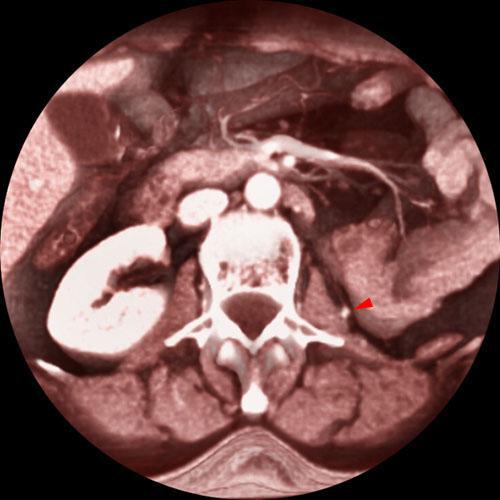

Recidiva local de hipernefroma

VR seccional. Visión axial caudal. TC contrastado en fase venosa, apreciándose una pequeña lesión nodular (punta de flecha), captante de contraste y pegada al músculo psoas, correspondiente a recidiva del hipernefroma